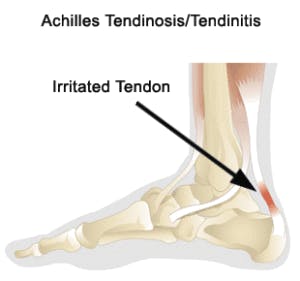

The Signs of Achilles Tendinitis Sydney Heel Pain hot sale, Achilles tendon injuries healthdirect hot sale, Back of Achilles Tendon Heel Pain Shoes Orthotics Home Treatment hot sale, Know the Symptoms of Achilles Tendonitis Tendinopathy Gait Happens hot sale, Back of Achilles Tendon Heel Pain Shoes Orthotics Home Treatment hot sale, Chronic Achilles Tendon Pain Diagnosis Treatment HSS hot sale, Achilles Tendinitis Symptoms Treatment hot sale, Heel Pain Causes Treatment and Prevention hot sale, Achilles Tendinitis Ankle Pain Foot Injury hot sale, Pain at the back of the heel The BMJ hot sale, Pain at the back of the heel How to figure out what s causing it and what to do about it hot sale, Achilles Tendon Injuries Johns Hopkins Medicine hot sale, Achilles Tendonitis Treatment in Gilbert Scottsdale Chandler Mesa Phoenix hot sale, Achilles Tendinitis in Children Causes and Treatment hot sale, Achilles Tendon Pain Symptoms Causes Treatment Exercises hot sale, Achilles Tendonitis Causes Symptoms Signs Gleneagles Hospital hot sale, HealthCrib THE FOOT Achilles tendinitis is a form of inflammation seen within the tendon of the calf muscle group gastrocnemius and soleus Typically seen in runners brought on by a hot sale, Why You Should Never Ignore Achilles Heel Painv Suncoast Orthopaedic Institute hot sale, Protecting Your Achilles Heel From Injury Dr Gordon Slater hot sale, Back of Achilles Tendon Heel Pain Shoes Orthotics Home Treatment hot sale, Home Remedies for Achilles Tendinitis Cornerstone Foot Ankle hot sale, Shooting pain store up achilles tendon hot sale, Achilles tendinitis Information Mount Sinai New York hot sale, Keeping Up Your Routine With Achilles Tendonitis Precision Foot and Ankle hot sale, Achilles Tendon Rupture Brisbane Physiotherapy hot sale, Pain In The Back Of The Heel What Could It Mean hot sale, How to Relieve Achilles Tendonitis in SECONDS hot sale, Achilles tendon rupture Wikipedia hot sale, Physiotherapy for Achilles Tendonitis Complete Care Physiotherapy Centre hot sale, Achilles Tendonitis Treatment in Gilbert Scottsdale Chandler Mesa Phoenix hot sale, Achilles Tendon Pain Symptoms Causes Treatment Exercises hot sale, Pain in the Back of the Heel Causes and Treatment hot sale, When to Worry About Calf Pain Causes and Warning Signs hot sale, Heel Pain Signs and Symptoms of Achilles Tendonitis Podiatrist in Walnut Creek hot sale, Achilles Pain While Running What It Means and What to Do hot sale.